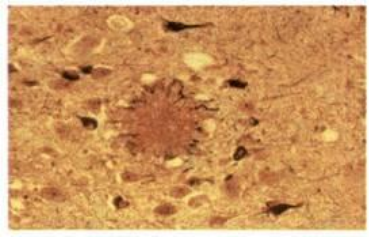

Οι περιοχές του εγκεφάλου που πραγματοποιούν συγκεκριμένες λειτουργίες έχουν εντοπιστεί με διάφορες τεχνικές. O φλοιός των ημισφαιρίων χωρίζεται σε κινητικές, αισθητικές και συνειρμικές περιοχές (εικ.14). Οι κινητικές περιοχές εντοπίζονται στο μετωπιαίο λοβό. Οι κινήσεις των σκελετικών μυών συγκεκριμένου τμήματος του σώματος ελέγχονται πάντα από καθορισμένη περιοχή στο οπίσθιο τμήμα του μετωπιαίου λοβού (εικ.15). Αισθητικές είναι οι περιοχές του φλοιού στις οποίες καταλήγουν νευρικές ώσεις από τους αισθητικούς νευρώνες. Εκεί αναλύονται και ερμηνεύονται, με τελικό αποτέλεσμα τη δημιουργία των αισθήσεων και των συναισθημάτων. Οι σωματικές ή γενικές αισθήσεις (θερμοκρασία, αφή, πίεση και πόνος) γίνονται αντιληπτές στην πρόσθια περιοχή του βρεγματικού λοβού. Όπως συμβαίνει και με τις κινητικές περιοχές, καθορισμένες περιοχές του βρεγματικού λοβού είναι υπεύθυνες για την αντίληψη των ερεθισμάτων που προέρχονται από συγκεκριμένα τμήματα του σώματος (εικ.15). Στο πίσω τμήμα του ινιακού λοβού εντοπίζεται το κέντρο της όρασης, και στον κροταφικό, το κέντρο της ακοής (εικ.14). Οι συνειρμικές περιοχές καταλαμβάνουν περισσότερο από το 50% της επιφάνειας του εγκεφαλικού φλοιού. Σχετίζονται με όλες τις ανώτερες πνευματικές λειτουργίες όπως είναι η μνήμη, η αιτιολόγηση, η έκφραση μέσω του λόγου, η κρίση, τα συναισθήματα (εικ.14).   εικ.14 Κινητικές, αισθητικές και συνειρμικές περιοχές του εγκεφάλου   Περιοχή Broca: υπεύθυνη για την παραγωγή του λόγου εικ.15α. Περιοχή ελέγχου εκούσιων κινήσεων (μετωπιαίος λοβός) β. Περιοχή γενικών αισθήσεων (βρεγματικός λοβός)   Πίνακας 2: Λειτουργίες των λοβών των ημισφαιρίων       Νόσος Alzheimer Η νόσος αυτή προσβάλλει στις ανεπτυγμένες χώρες το 5% των ατόμων ηλικίας πάνω από 65 ετών και το 20% των ατόμων ηλικίας πάνω από 80 ετών. Οδηγεί στην άνοια (προοδευτική απώλεια των πνευματικών λειτουργιών, ανεξάρτητη από αυτήν που συνοδεύει τη γήρανση του εγκεφάλου). Τα άτομα που προσβάλλονται από τη νόσο εμφανίζουν απώλεια μνήμης, μειωμένη ικανότητα σκέψης και λογικής αιτιολόγησης, δυσκολίες στην επικοινωνία με άλλα άτομα, ακόμα και ανικανότητα στην εκπλήρωση απλών καθημερινών δραστηριοτήτων. Στους πάσχοντες παρατηρήθηκαν ανωμαλίες σε νευρώνες, κυρίως σε περιοχές του φλοιού των ημισφαιρίων. Στις περιοχές αυτές παρατηρούνται εξωκυτταρικές εναποθέσεις (αμυλοειδείς πλάκες), λόγω συσσώρευσης μίας μικρού μοριακού βάρους πρωτεΐνης, της β-αμυλοειδούς πρωτεΐνης. Η αυξημένη συγκέντρωση της πρωτεΐνης αυτής οδηγεί πιθανώς στη λύση των λυσοσωμάτων, με συνέπεια την καταστροφή των νευρικών κυττάρων. Η πρωτεΐνη αυτή αποτελεί τμήμα μιας άλλης πρόδρομης πρωτεΐνης, της ΑΡΡ (Amyloid Precusor Protein), που φυσιολογικά βρίσκεται στην κυτταρική μεμβράνη των νευρώνων και άλλων κυττάρων. Μία μορφή της νόσου φαίνεται να είναι κληρονομική. Έχει απομονωθεί γονίδιο στο 21ο ζεύγος των χρωμοσωμάτων, το οποίο καθορίζει τη δομή της πρόδρομης πρωτεΐνης. Η γονιδιακή αυτή θέση αποκτά ιδιαίτερο ενδιαφέρον, διότι όλα σχεδόν τα άτομα που πάσχουν από το σύνδρομο Down (τρισωμία 21) και επιβιώνουν μετά τα 35 έτη εμφανίζουν συμπτώματα της ασθένειας Alzheimer.     Αμυλοειδής πλάκα (στο κέντρο της φωτογραφίας) σε εγκεφαλικό ιστό ατόμου που πάσχει από νόσο Alzheimer   Απεικόνιση PET εγκεφάλου υγιή ενήλικα (αριστερά) και ασθενή που πάσχει από νόσο Alzheimer (δεξιά). Η αυξημένη επιφάνεια σκουρόχρωμων περιοχών στην εικόνα δεξιά δείχνει διαταραχές στην εγκεφαλική δραστηριότητα